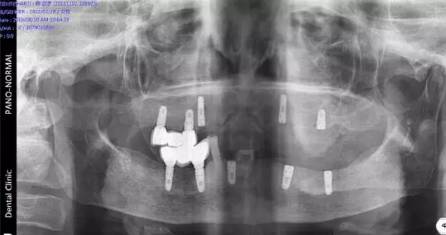

現(xiàn)場北京口腔醫(yī)學(xué)會(huì)專家、德國專家親自接診,經(jīng)過口腔CT確診,老人全口牙缺失,為其制定CHEESE德國激光種植技術(shù),8根牙根種出滿口好牙,不僅當(dāng)天種好,還省了錢。

(現(xiàn)場口腔CT拍片)